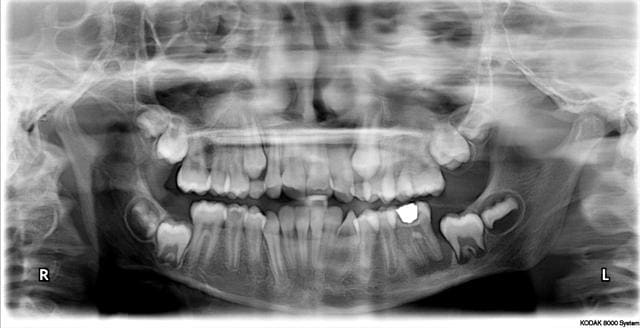

Patient 11ans, a vu sa dentiste habituelle il y a 3 mois pour l'amalgame sur 36...elle l'a envoyé chez l'odf les soins étant finis.

Endo, extraction 36? quid de 37?

45 est prévue.

qu'elle ait envoyé sa patiente chez l'odf pr un avis sur la possibilité de tracter 37 (puisque le germe de 38 est présent) et l'organisation du plan de traitement(naïve et crédule sur la conscience pro? sans doute)

en ts cas c'est ce que j'aurais fait avant de décider l'extraction ou la conservation(avec qd mme une grosse preference pr extraction-suivi odf)

si la conservation est décidée(en accord avec l'odf: quelle est l'implication sur la reussite de la traction de 37 en cas d'echec à 1 an ou plus?) il faut savoir que la réussite n'est pas acquise,qu'il y aura surveillance à 1 semaine,1 mois,3 mois,6 mois puis ts les 6 mois pdt 5 ans,qu'un comblement n'est pas exclu s'il reste une perte osseuse importante par la suite,que malgré tout cela,il peut y avoir echec et on reviendra peut être à de l'odf ou de l'implanto, qu'il faut que les parents en soient conscients et motivés,etc,etc...

Mais la chir me semble un peu risquée pour le germe de 37.